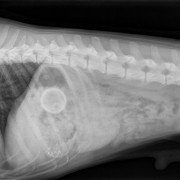

De malteser Daisy, een teefje van 10 jaar, kwam op 27 mei 2010 met blaasklachten op de praktijk. Dit is niet de eerste keer; in 2008 heeft zij ook al blaasproblemen gehad. Bij het onderzoek blijft op de röntgenfoto dat er een groot aantal grote en kleine stenen in de blaas aanwezig zijn. Deze stenen irriteren de blaaswand wat een blaasontsteking en pijn geeft. Ook kunnen deze stenen gemakkelijk in de plasbuis vastlopen waardoor het plassen bemoeilijkt wordt of zelfs helemaal niet meer lukt. We hebben Daisy operatief van deze stenen af geholpen. Daarna ging het  stukken beter. Daisy heeft zelf nog enkele kleine steentjes uitgeplast. Ze krijgt speciaal dieet om de vorming van deze stenen in de toekomst te voorkomen.

Meerdere blaastenen zichtbaar op de röntgenfoto (linksonder)